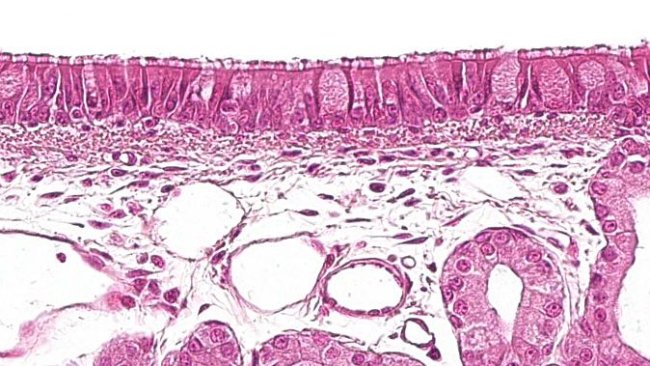

Schéma d'activation du système immunitaire commun des muqueuses

En explorant les mécanismes du système immunitaire commun des muqueuses, les vaccins administrés par voie orale peuvent activer des réponses immunitaires coordonnées dans différentes zones muqueuses de l'organisme. Dans cet article, nous expliquons comment l'activation locale dans le GALT déclenche des effets protecteurs dans les tissus muqueux distants, tels que les voies respiratoires, élargissant ainsi la portée de la protection immunitaire.